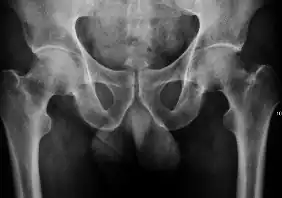

Projectional radiography ("X-ray") is the first imaging technique of choice in hip pain, not only in older people with suspected osteoarthritis but also in young people without any such suspicion. In this case plain radiography allows categorization as normal hip or dysplastic hip, or with impingement signs, pincer, cam, or a combination of both.[1]

X-Ray

Projectional radiography ("X-ray") is currently useful not only in older people in whom osteoarthritis of the hip is suspected but also in younger people without osteoarthritis, who are being evaluated for femoroacetabular impingement (FAI) or hip dysplasia.[1]

Plain radiography allows us to categorize the hip as normal or dysplastic or with impingement signs (pincer, cam, or a combination of both). Besides these, pathologic processes like osteoarthritis, inflammatory diseases, infection, or tumors can also be identified (Figure 1).[1]

Figure 1.

-

Radiography in normal hip -

X-ray in pincer impingement type of hip dysplasia -

X-ray of cam -

Hip in osteoarthritis -

Septic arthritis

![Figure 2A. Normal hip.[1]](./_assets_/X-ray_of_measurements_on_a_normal_hip.jpg)

![Figure 2B. Hip dysplasia.[1]](./_assets_/X-ray_of_measurements_in_hip_dysplasia.jpg)